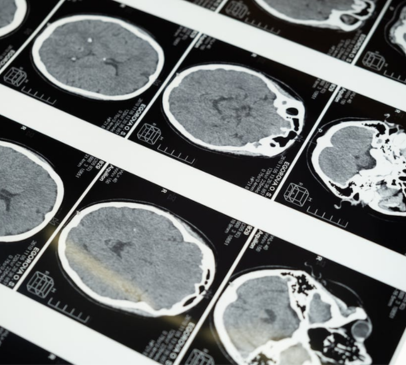

New Lancet Commission on dementia, including TBI as risk factor Main Image

Traumatic brain injury (TBI) has been discussed as one of 14 risk factors contributing to dementia risk in a new 2024 Lancet Commission, Dementia prevention, intervention, and care: 2024 report of the Lancet standing Commission.